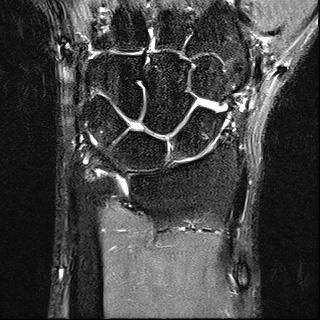

mri는 23년 부분파열 당시

2023년 MRI 영상을 보면, 삼각섬유연골복합체(Triangular Fibrocartilage Complex, TFCC)에 전반적인 신호 변화와 함께 척골 부착부 근처의 손상 소견이 확인됩니다. 당시 봉합술을 시행한 것은 임상적으로 타당한 판단이었습니다. 이후 경과가 양호하다가, 2025년 12월 요골·척골 원위부 골절이 발생한 점이 현재 상황의 핵심입니다.